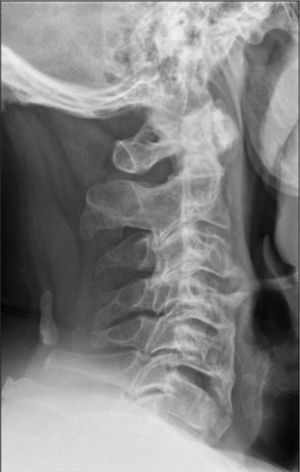

Our hospital performed X-rays of the cervical, dorsal, lumbar and pelvic spine which showed a calcification of the anterior common vertebral ligament with preservation of the disc spaces (Figs. 1 and 2).

Forestier's disease is related to abnormal bone growth.1–3 The main disease symptoms is calcification of the longitudinal ligaments of the spine, involving at least 4 contiguous vertebrae. Other criteria are the preservation of intervertebral disc spaces and the absence of inflammatory changes in intrapophysary or sacroiliac joints.4–6